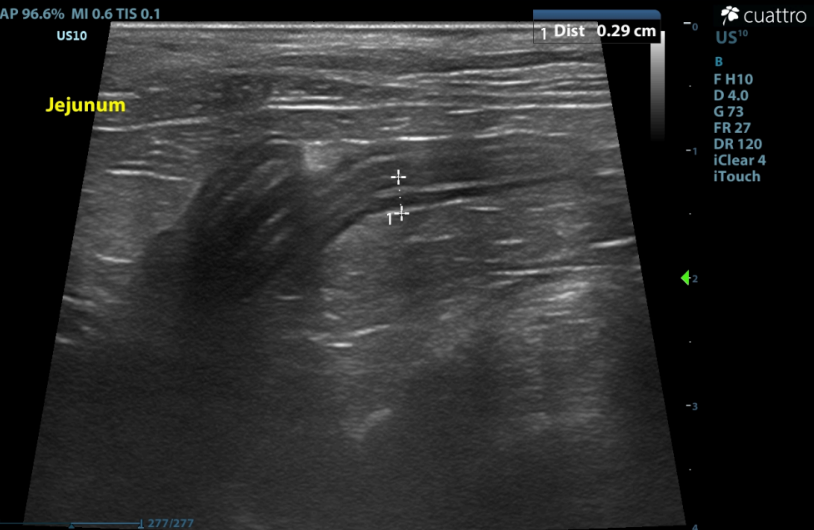

Intestinal Tract - Many to most loops of intestine are prominent to mildly thickened. Many have abnormal layering with prominent disproportionate thickening of the muscularis layer. No obstruction or masses seen.

Maximum wall thickness: Stomach-1.9 mm; Duodenum - 3.0 mm; Jejunum - 2.9 mm; Colon - 1.1 mm.

(normal wall thickness ~2.2-2.5mm, > 2.8mm abnormal Norsworthy/Estep et. al. JAVMA, Vol 243, No.10, November 15, 2013)